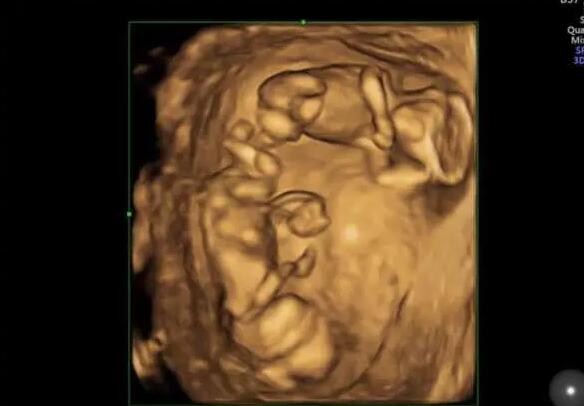

山東試管供卵 山東生殖醫(yī)院三代試管多少錢 ‘四維女孩三條線圖片’

在IVF中,囊胚是胚胎體外培養(yǎng)的終末階段,它通常形成于卵子受精后的第5-7天。自然狀態(tài)下,人類胚胎以囊胚的形式植入母體。因此,不難理解,進(jìn)行囊胚移植,能獲得較高的胚胎植入率。